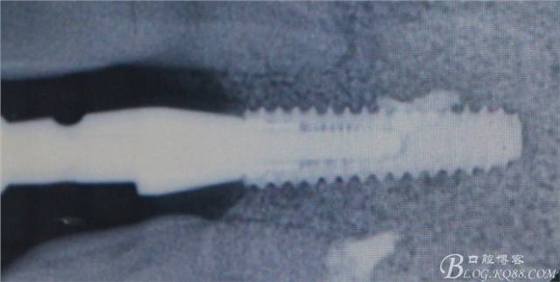

術(shù)后X光片。

骨高度穩(wěn)定。